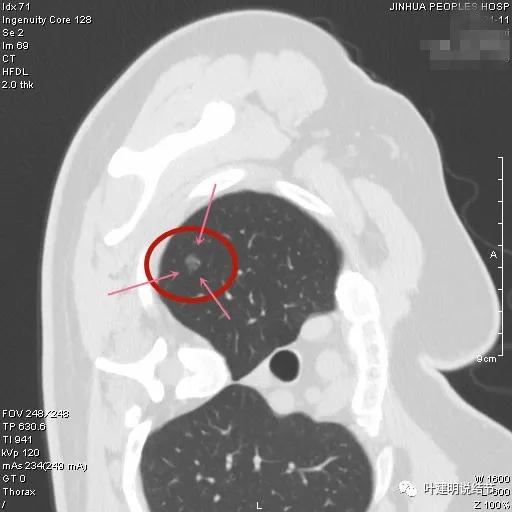

病灶密度较低,膨胀性略,瘤肺边界在靶扫描上还是显得有些清晰的

病灶瘤肺边界清,密度偏低,有点散,但有微小血管进入(桔色箭头)

病灶整体密度较低,但轮廓较清,内部密度不大均匀,显得杂乱

不均质的偏低密度磨玻璃结节,轮廓清